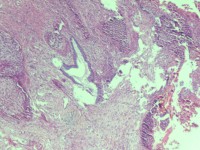

性别

女

年龄

43岁

临床诊断

宫颈病变

一般病史

宫颈癌筛查:hpv16(+))

标本名称

宫颈组织

大体所见

灰白色组织

老师们看看,高级别累腺吗

高级别累腺,不除外局灶早期浸润

高级别累及腺体